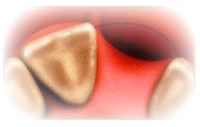

Корни естественных зубов погружены в кость челюсти, которая обеспечивает надежную опору для функционирования зубов. При утрате или удалении зубов кость, которая осуществляла их поддержку, больше не выполняет данной функции и начинает рассасываться

Стоматологические имплантаты представляют собой замену корней зубов и, осуществляя стимуляцию кости посредством нагрузки, предотвращают ее атрофию, которая обычно возникает при утрате зуба. Кость челюсти, фактически, срастается с имплантатом и создает крепкую основу для ортопедической конструкции, которая выглядит и функционирует также как естественные зубы. Видимая часть естественного зуба называется "коронкой". Корни Ваших зубов погружены в кость, которая обеспечивает надежную опору и позволяет Вам кусать и жевать Зубные имплантаты представляют собой замену корней и являются опорами для искусственных коронок.

При утрате зуба во фронтальном отделе полости рта, где кость очень тонкая, кость обычно рассасывается очень быстро, что приводит к западанию или проваливанию кости и десны. Очень часто такие дефекты видны при улыбке. Если при отсутствии фронтального зуба Вы предпочтете установить мостовидный протез, в конечном итоге коронка в области отсутствующего зуба будет выглядеть неестественно, поскольку кость и десны начинают проваливаться, оставляя зуб без видимой поддержки. Когда утраченный зуб протезируют с помощью имплантата, то последний функционирует в качестве корня и осуществляет опору для коронки,что предотвращает атрофию кости, которая обычно происходит при удалении зуба.